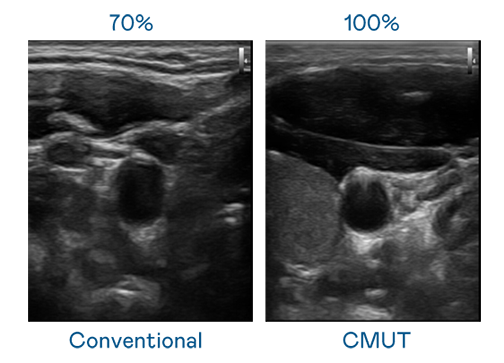

CMUT 技术是一种用电容式微机电元件来产生超音波讯号的技术。与传统 PZT 压电式技术相比,CMUT 频宽增加 30%,更宽频的超音波讯号让影像解析度大幅提升,是实现高影像品质医疗超音波扫描、促进精准医疗发展的关键技术。

大频宽带来超清晰影像

超音波影像的解析度高低,首先取决于探头能发出的讯号频宽。麻花豆传剧媒国产剧在线观看完整 CMUT 可提供高清晰的超音波讯号,提供高频宽、高灵敏度、影像纹理细节更高的超音波影像,协助医护人员缩短影像判读时间及利用精准的医疗影像进行诊断。